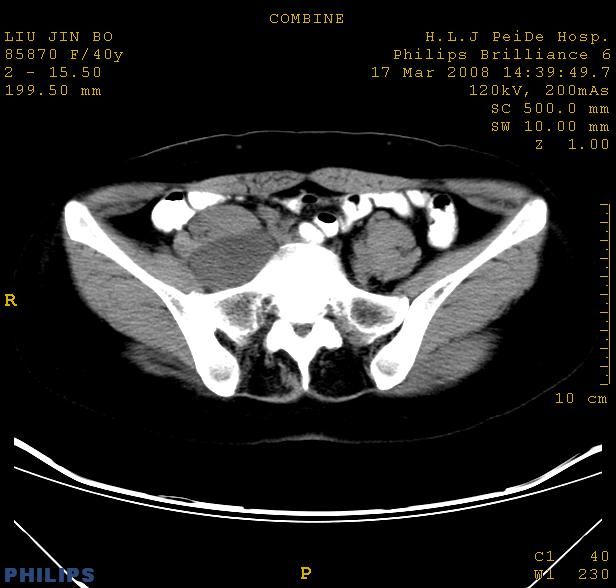

以下是引用qiuleiyu在2008-4-27 12:36:00的发言:[br]支持;右侧腰大肌后方神经源性肿瘤可能大,神经节细胞瘤?

以下是引用形影不离在2008-4-27 14:11:00的发言:[br]1.考虑右侧腰大肌脓肿。[br]2.左侧附件区炎症。[br]3.子宫增大,建议:进一步检查。